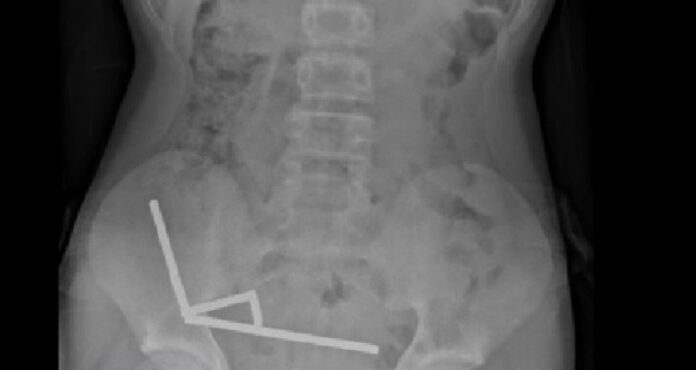

Exames revelaram que os ímãs haviam se agrupado em quatro correntes na parte inferior direita do abdômen, unindo diferentes seções do intestino com sua força magnética, segundo o relatório, que observou que algumas imagens foram distorcidas pelos ímãs. Os médicos então procederam com uma cirurgia exploratória.

Durante o procedimento, os cirurgiões descobriram que as correntes de ímãs estavam causando necrose por pressão – morte do tecido por pressão prolongada – em partes do intestino delgado e grosso. Eles conseguiram remover os ímãs, mas o menino precisou ter parte do intestino removido. Ele passou oito dias se recuperando no hospital antes de receber alta, informou o relatório.